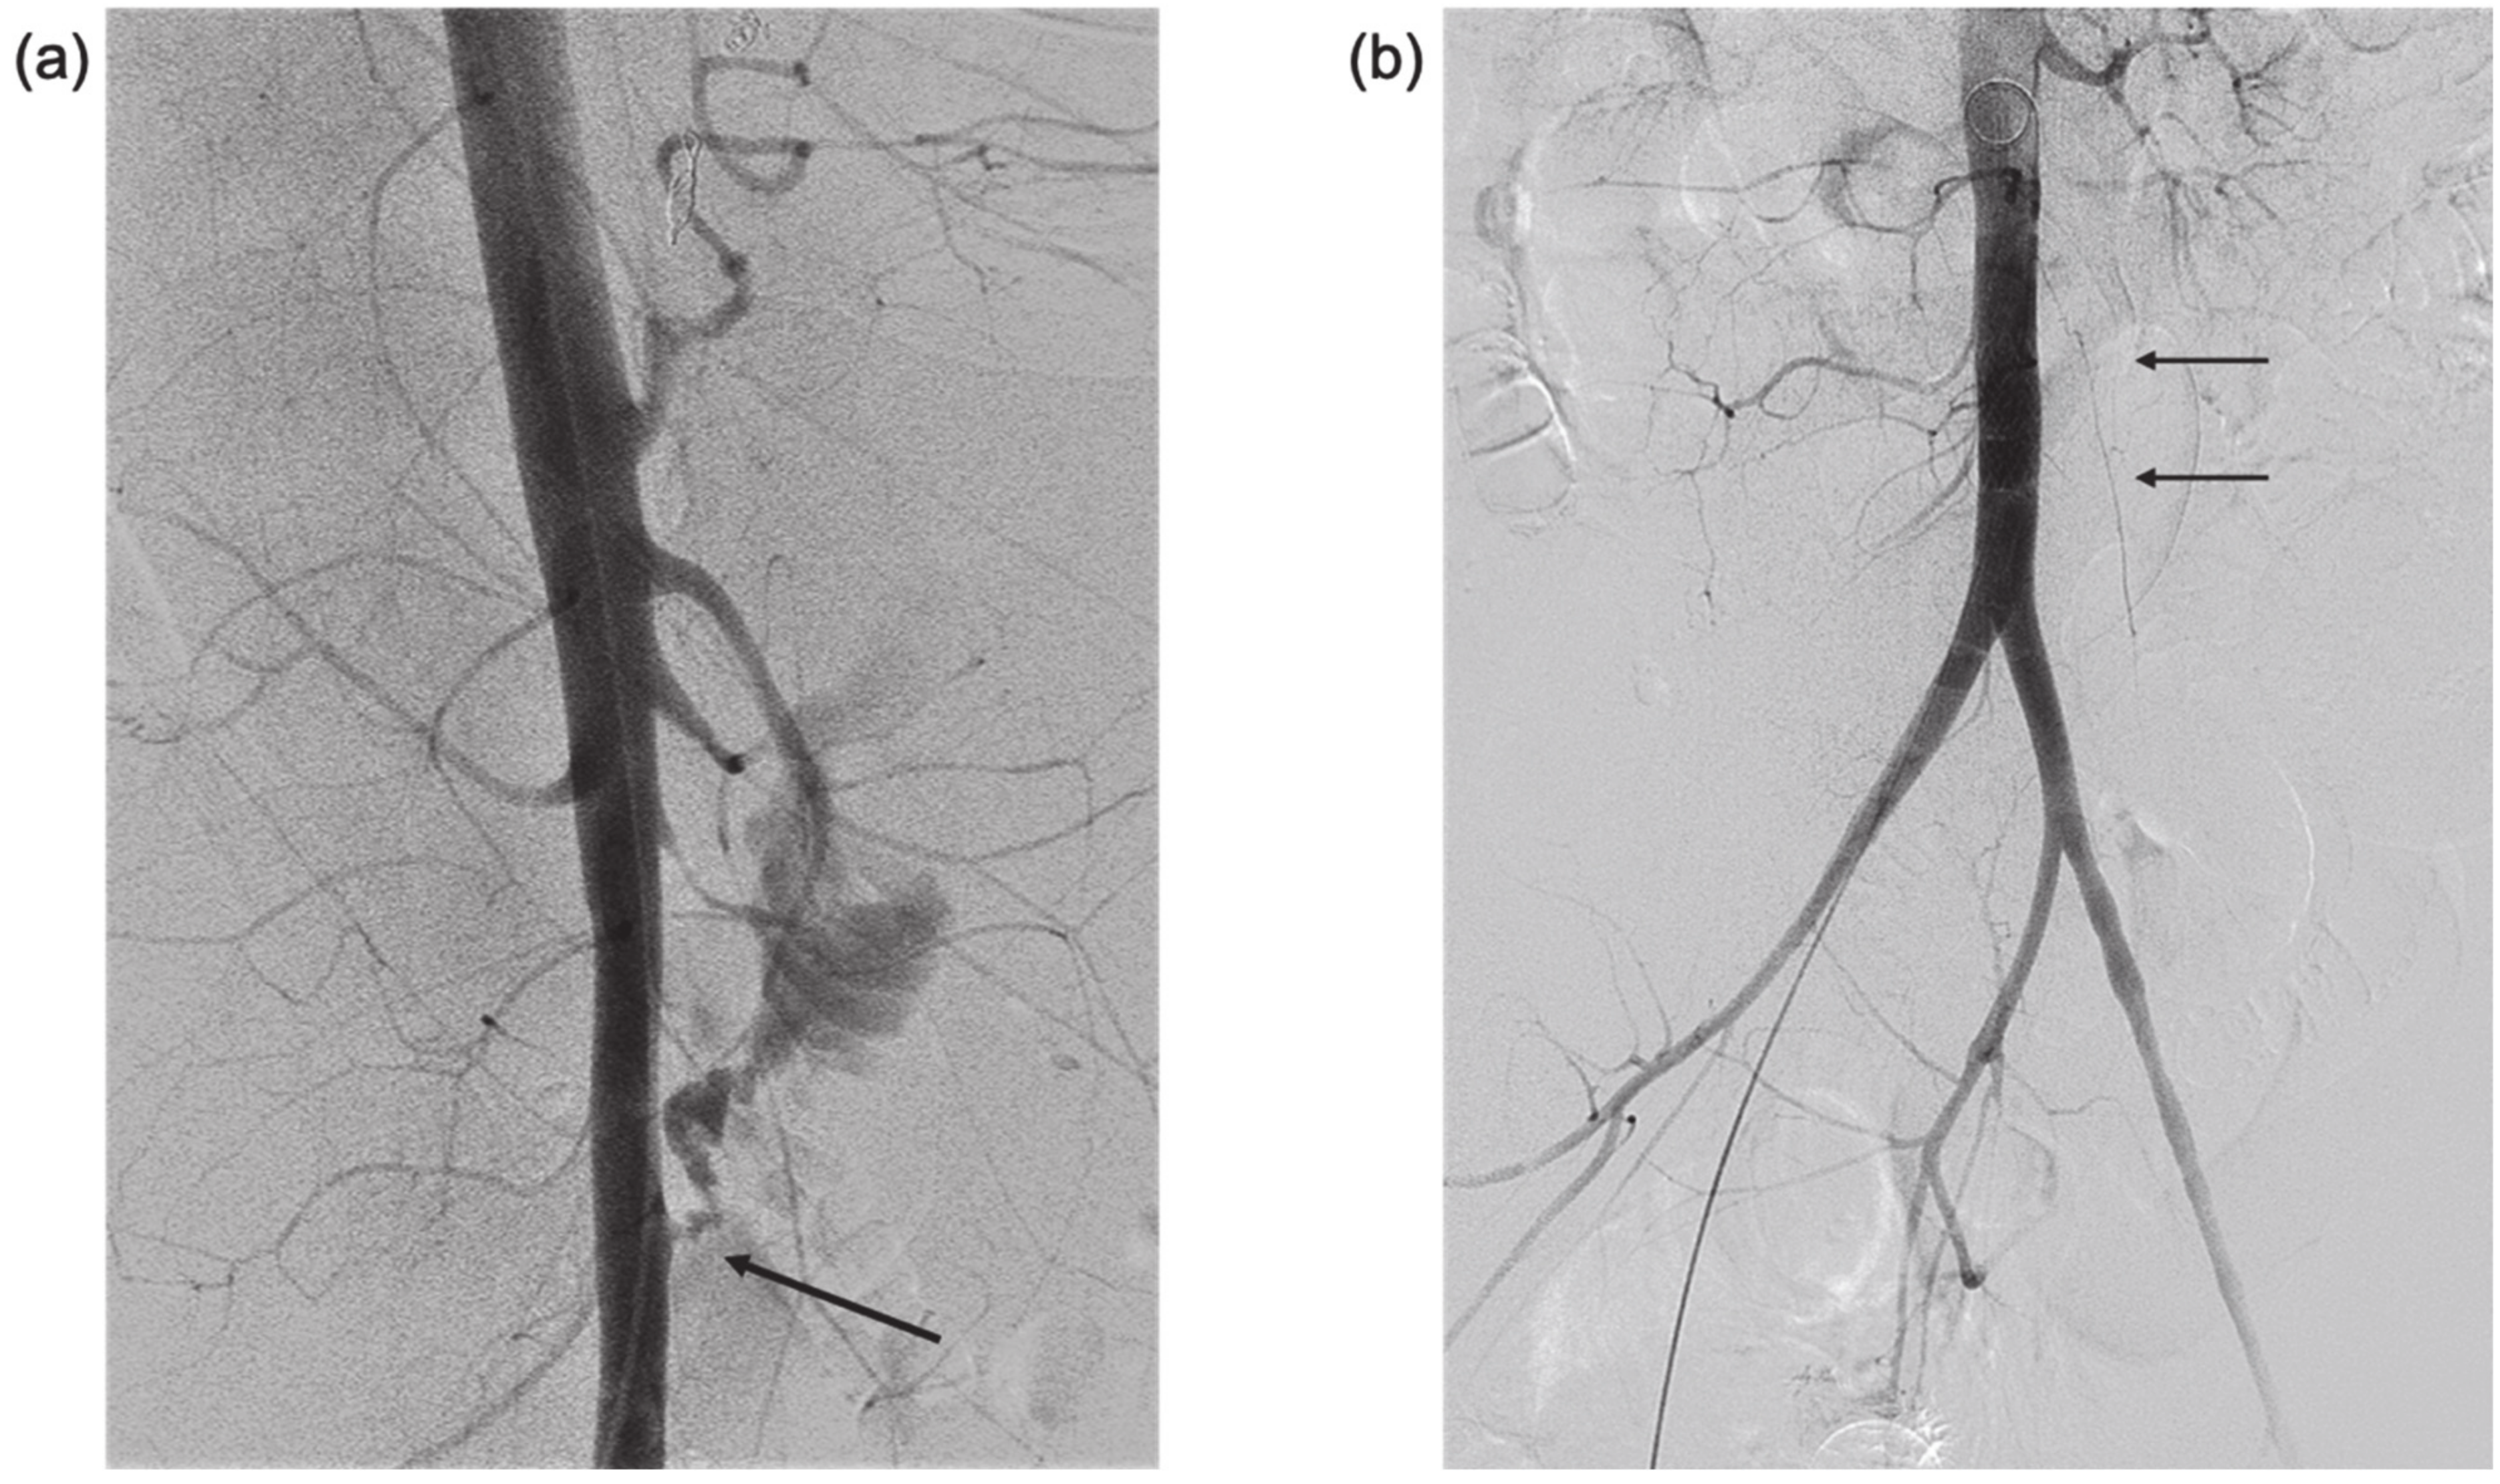

Figure 1. (a) CT + intravenous contrast, three months prior to bleeding event, showing the extent of disease (white arrow) around the abdominal aorta (black arrow) and relationship to duodenum (sagittal and axial views). (b) CT of the spine one month prior to bleeding. Sagittal and axial views. With retrospect, air (encircled) was identified between the aorta (star) and duodenum (arrow), highly suspicious for aorto-duodenal fistula.